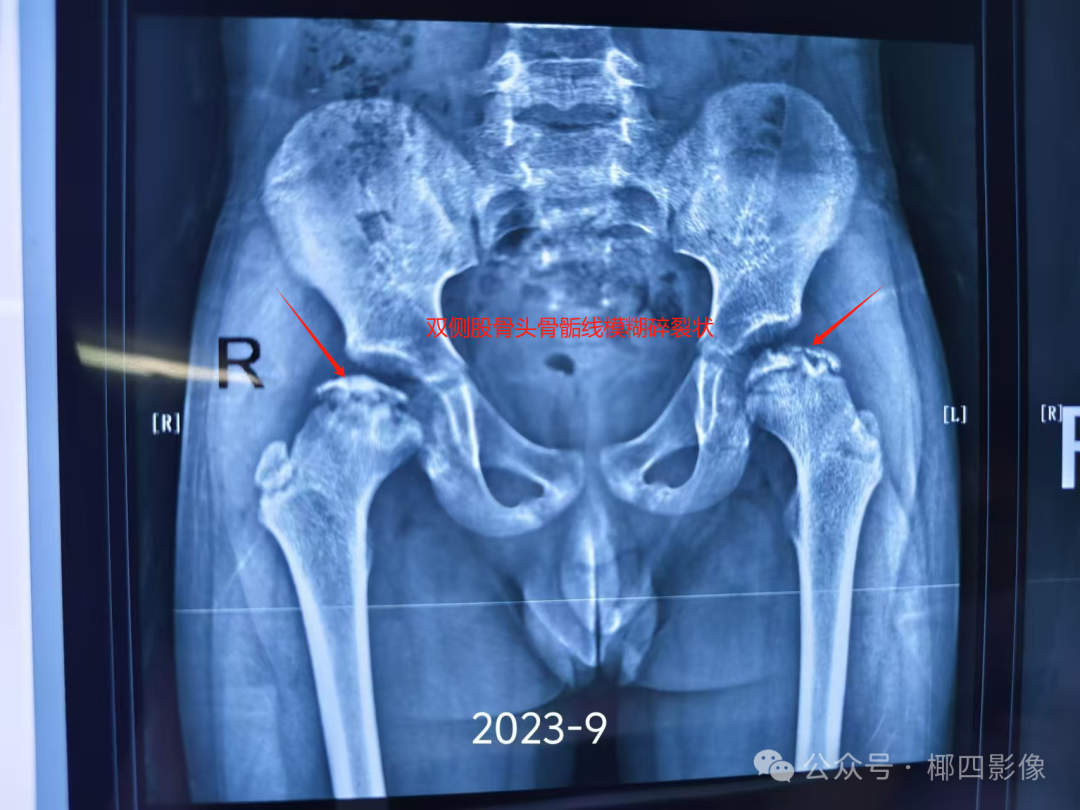

股骨头坏死可以自愈吗

股骨头坏死一般无法自愈,但儿童因外部因素导致的病例自愈可能性较大,成年人自愈能力较弱,需积极治疗 以下是具体分析股骨头坏死的治愈标准股骨头坏死的治愈需满足多项条件,包括休息时疼痛消失行走或负重时疼痛减轻或消失髋关节功...